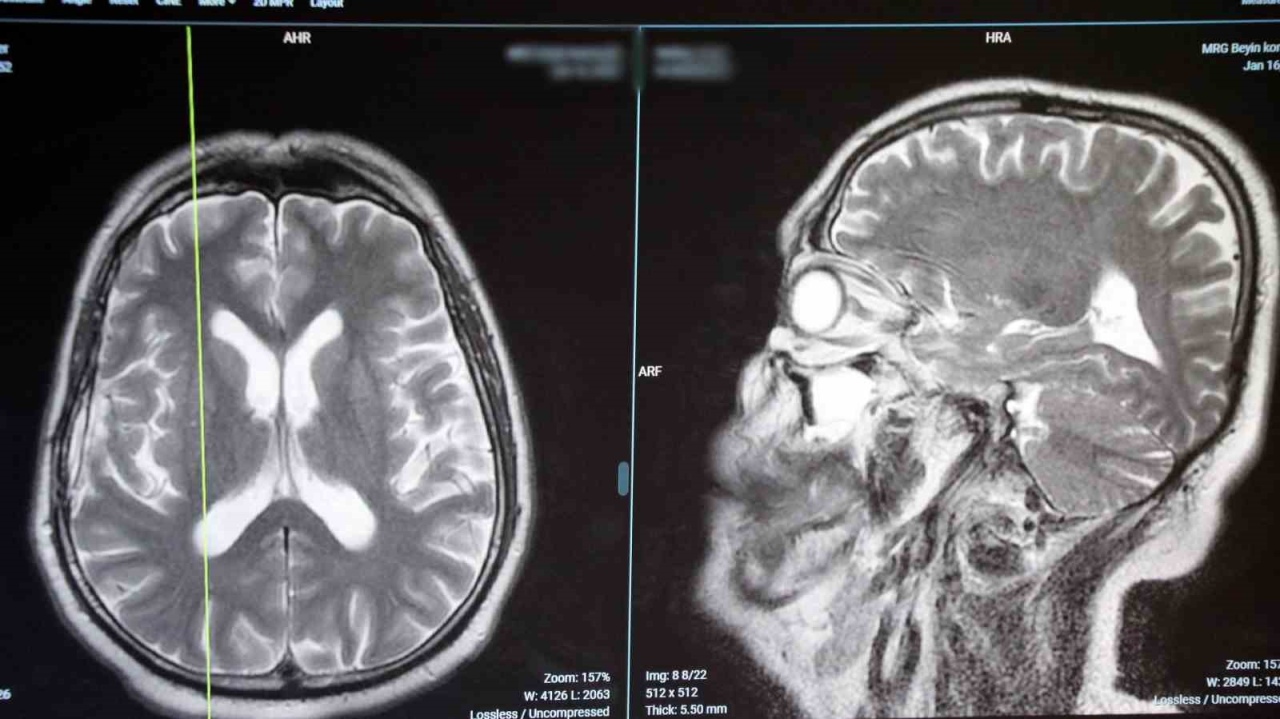

Beyin ve Sinir Cerrahisi Uzmanı Dr. Öğr. Üyesi Cevdet Gökçek, beyin tümörlerinde görülebilen baş ağrısı, kusma ve nöbet gibi bulguların erken teşhis açısından önemli olduğunu belirtti. Medipol Sağlık Grubu tarafından yapılan açıklamada, beyin tümörlerinin beynin kendi dokusundan, çevresindeki zarlardan veya farklı organlardaki kanserlerin beyne yayılmasıyla gelişebildiği aktarıldı.

Tanıda görüntüleme yöntemlerinin belirleyici olduğuna dikkat çeken Gökçek, kapalı alan korkusu olan hastalar için tomografinin kısa sürede bilgi sağlayabildiğini, ancak beyin tümörlerinin yerinin ve yapısının net şekilde görülebilmesi için MR’ın gerekli olduğunu vurguladı.